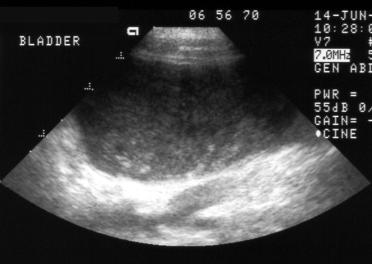

Ultrasound

Ultrasound (sonogram) is a tool that allows

noninvasive imaging of internal organs often without

the need for sedation or anesthesia.  In conjunction

with radiographs (X-rays), laboratory tests, history

and physical examination our veterinarians can

diagnose a wide variety of conditions.  Ultrasound

guided biopsies and aspirates are an option for

gathering samples from all species of pets.  It is

useful as an aid in managing and diagnosing

complex internal medicine cases, cardiac cases,

thoracic disease, urinary disease and reproductive

medicine.